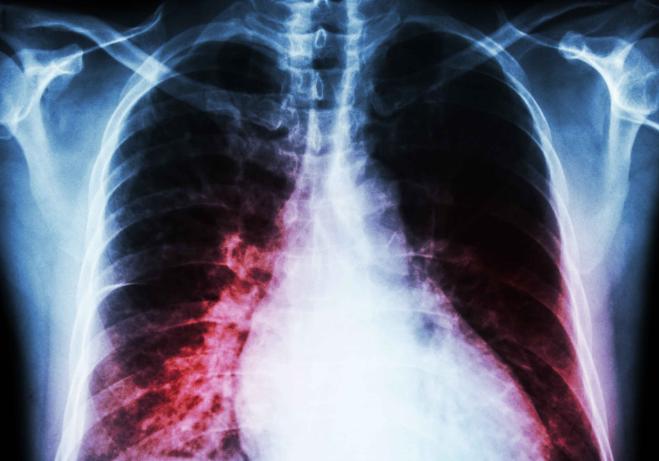

患者主要表现为阵发性、刺激性呛咳,无痰液排出、痰液中也无明显血丝。在进行x线检查时,能看到阶段性的侵润影!

所以,在出现肺炎症状之后,医生都会建议患者进行x片、血常规等多方面检查,其目的不是为了赚钱,而是为了确定所患肺炎的性质,并进行针对性的治疗。如果盲目使用药物、滥用抗生素,反而会延误病情诊断和治疗,甚至会给身体造成其他伤害。